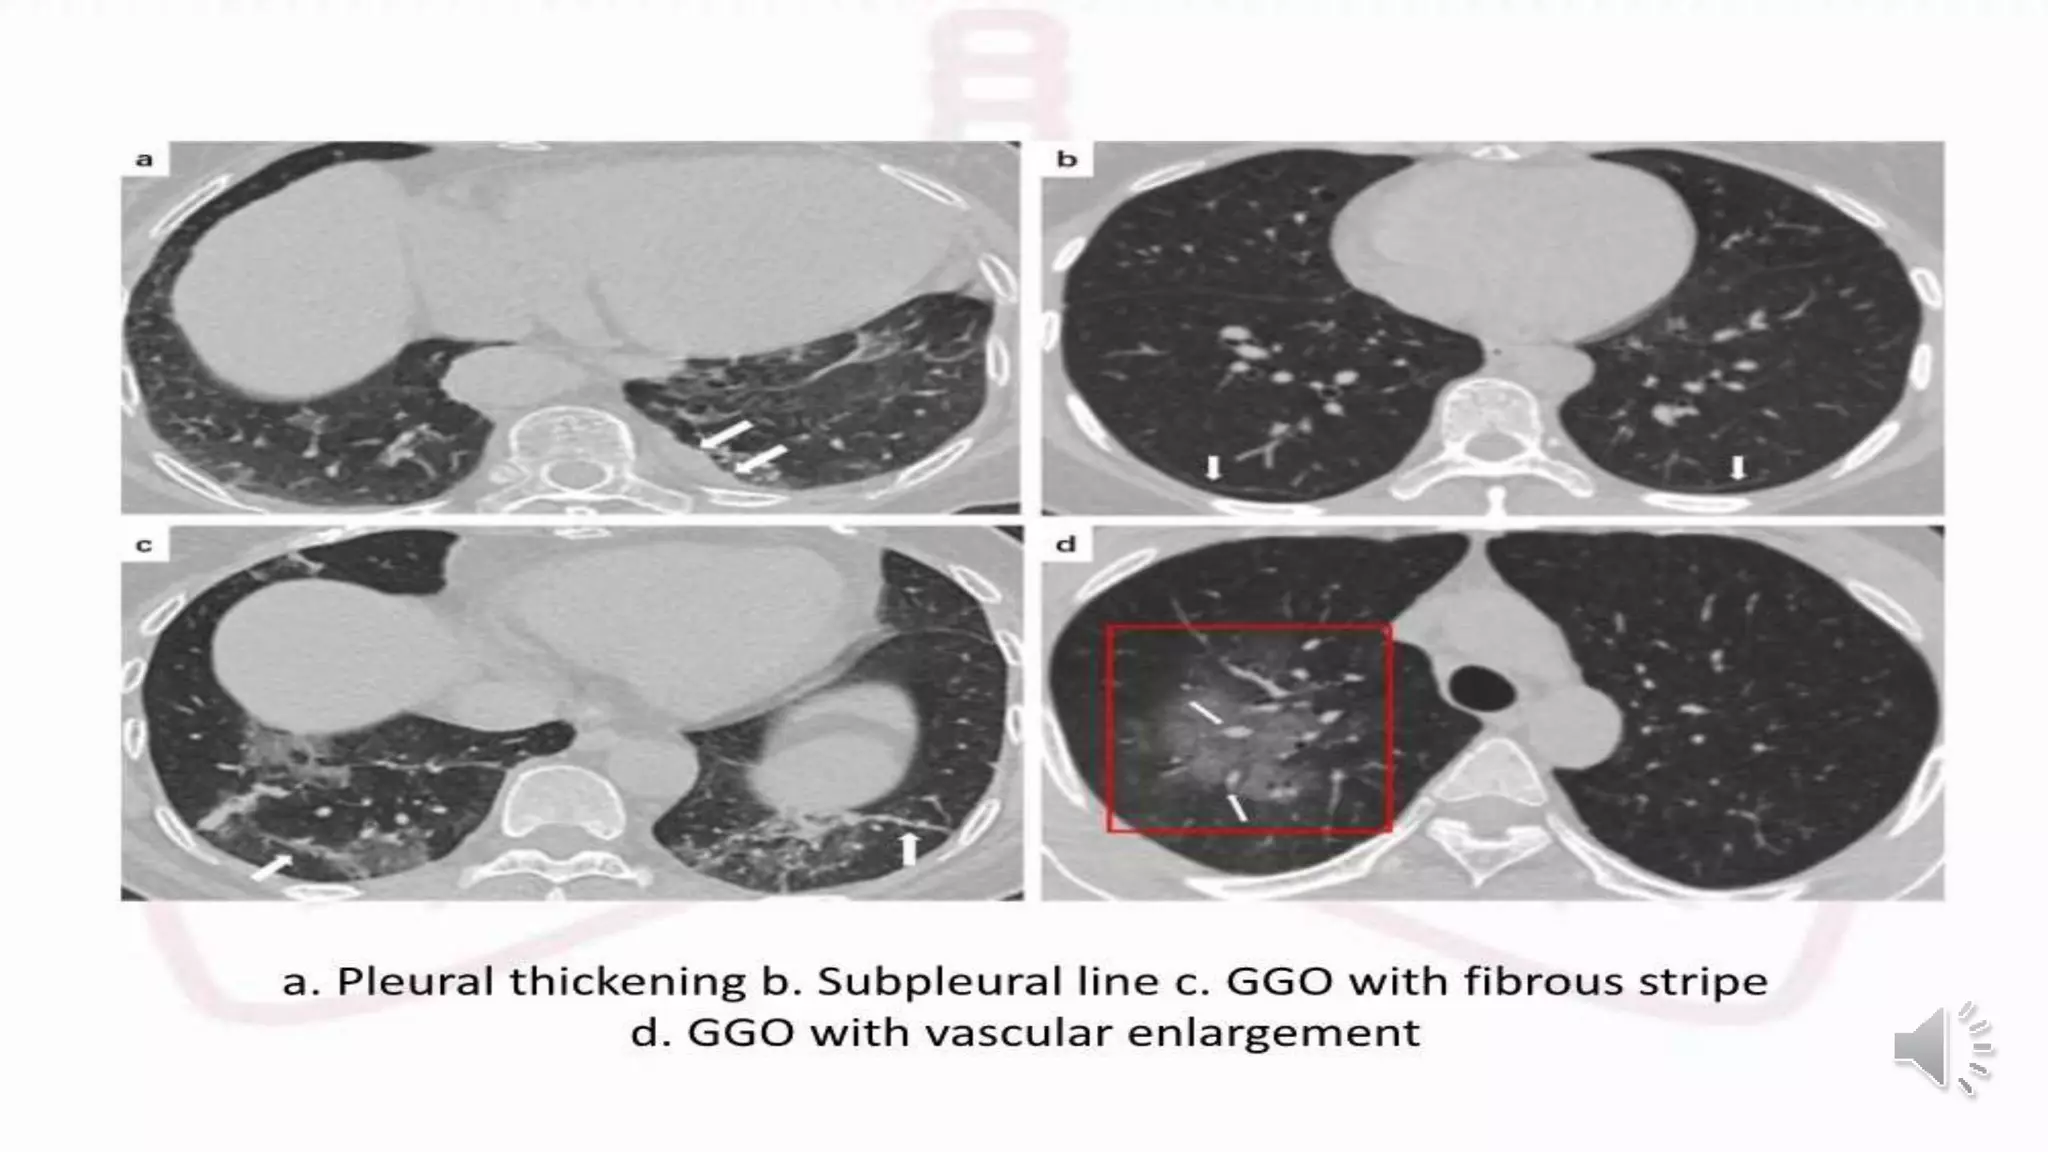

Table 5 CT and ultrasonographic features of COVID-19 pneumonia

Lung CT Lung ultrasound

Thickened pleura Thickened pleural line

Ground glass shadow and effusion B lines (multifocal, discrete, or confluent)

Pulmonary infiltrating shadow Confluent B lines

Subpleural consolidation Small (centomeric) consolidations)

Translobar consolidation Both non-translobar and translobar consolidation

No Pleural effusion No Pleural effusion

More than two lobes affected Multilobar distribution of abnormalities

Negative or atypical in lung CT images in

the super-early stage, then diffuse

scattered or ground glass shadow with

the progress of the disease, further lung

consolidation

Focal B lines is the main feature in the early stage and in

mild infection; alveolar interstitial syndrome is the main

feature in the progressive stage and in critically ill

patients; A lines can be found in the convalescence;

pleural line thickening with uneven B lines can be seen in

patients with pulmonary fibrosis